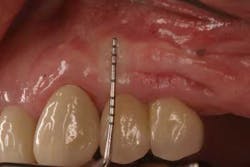

Fig. 1: Soft tissue recession around a dental implant restoration due to a deficiency in soft tissue volume.